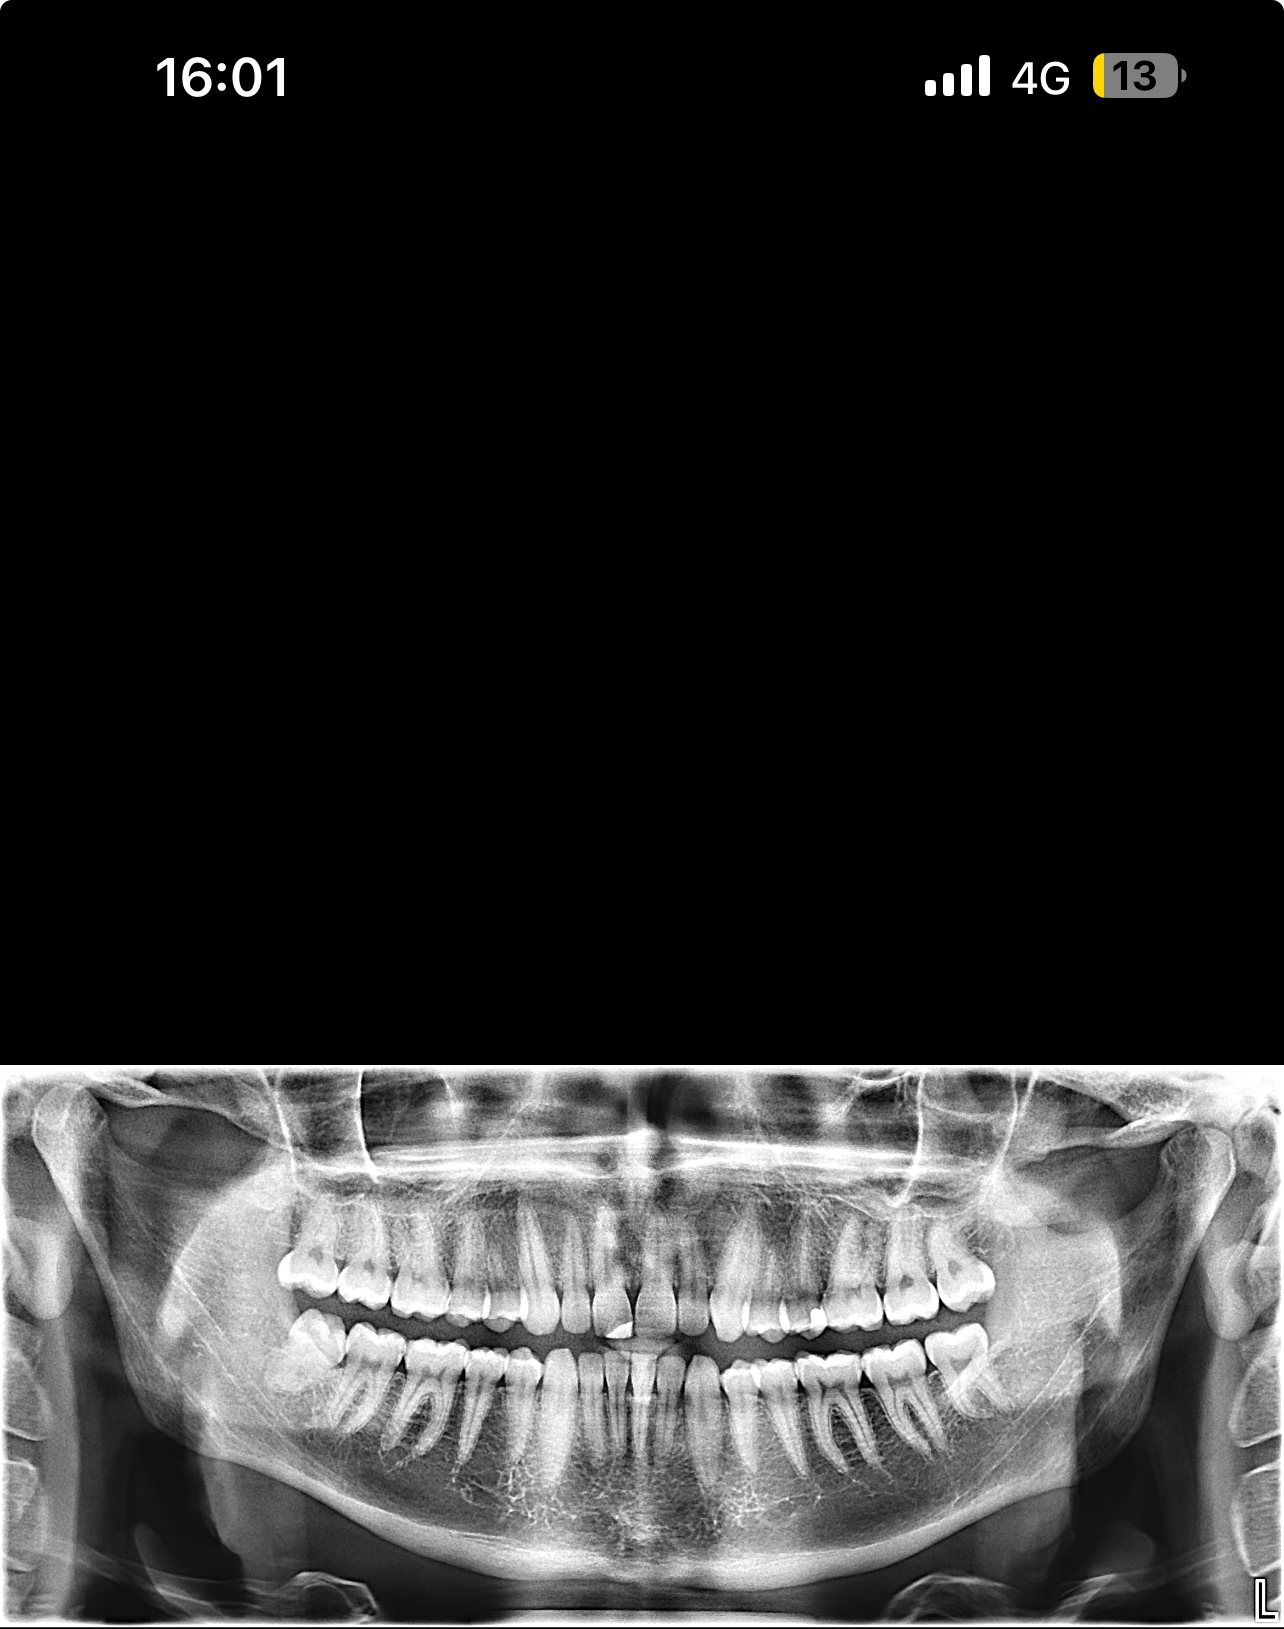

Hello, I’m looking for advice on genioplasty vs DJS. I was planned for a genio 7mm horizontal and squaring of chin on may 11th. I got a second opinion because I thought the oralmaxillofacila surgeon doing my genio might have been downplaying my mandible/maxilla recession. The second opinion oomfs surgeon said that genio would only be a camouflage and for my high expectations, might disappoint me, and I’m starting to think it will. My midface is flat and my mandible from side profile looks short and awful. The problem I have is DJS is a huge commitment for a bigger gain in a year-year and a half time. It’s a lot to take in. But I really don’t want to live my whole life with recessed jaws, I don’t want a soft youthful boyish look especially because I’m getting into my mid 20s, I hate my side profile a lot. Genio will help but I’m extremely worried I’ll be really disappointed, and I can’t really go back if I commit. Looking for advice on if I should go with the genio, see improvement now (which I care a lot about) and get a rhino/septoplasty to fix my deviated septum and be capped by by midface/mandible recession but decently improved, or If I should look awful for another year and a half with braces and my current recession but have the functional and aesthetic benefit of djs at the end. I have extremely bad breathing issues especially during exercise and pretty bad sleep issues, but I don’t know how much to that is down to allergies/deviated septum as opposed to airway issues. I just don’t know what to do, I’ll include my ceph/ct scans and side/front profile photos, would really appreciate guidance on what to do, was thinking of frauding with filler for a year before getting djs, or getting real structural change through rhino braces and genio that would all be down within 7-9 months, thankyou .

• IMG_3953.jpeg

IMG_3953.jpeg

1.7 MB · Views: 0